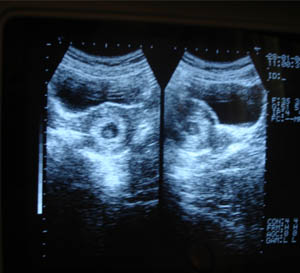

1st trimester obstetric ultrasonography

The routine includes that confirm the number of gestation. Locate its position (r/o ectopic). Measure CRL crown rump length & match with the h/o LMP (last menstrual period)